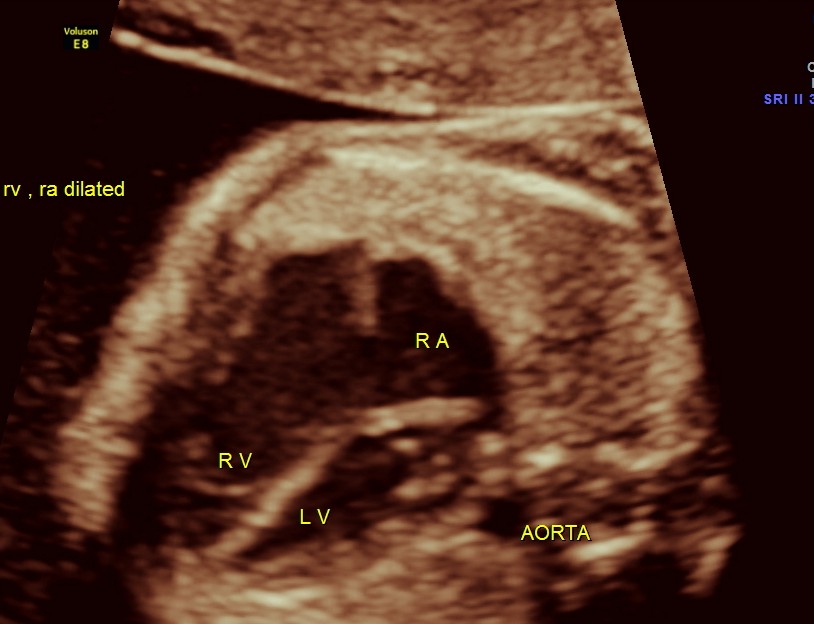

The cardiac axis appeared to be abnormal .

4 chamber view is given below .

Under normal circumstances the chamber in front of descending aorta is left atrium ; and the aorta arises from the left ventricle which has no trabeculations ; the pumonary artery which divides into the two branches arises from the anterior right ventricle and crosses over the aorta .

THE DIAGNOSIS OFFERED WAS TRANSPOSITION OF GREAT ARTERIES WITH VENTRICULAR SEPTAL DEFECT

Transposition of the great arteries (TGA) is the most common cyanotic congenital heart lesion that presents in neonates. The hallmark of transposition of the great arteries is ventriculoarterial discordance, in which the aorta arises from the morphologic right ventricle and the pulmonary artery arises from the morphologic left ventricle.